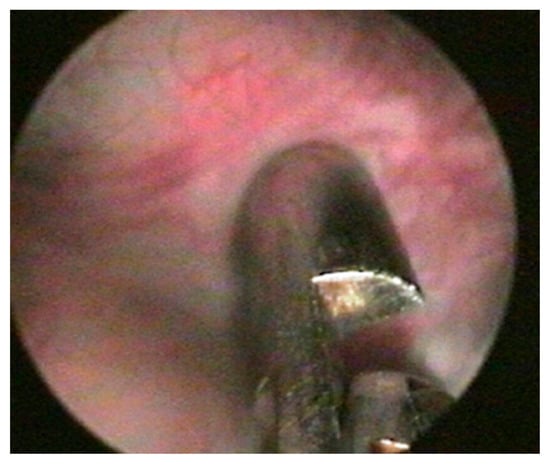

2. Materials and Methods